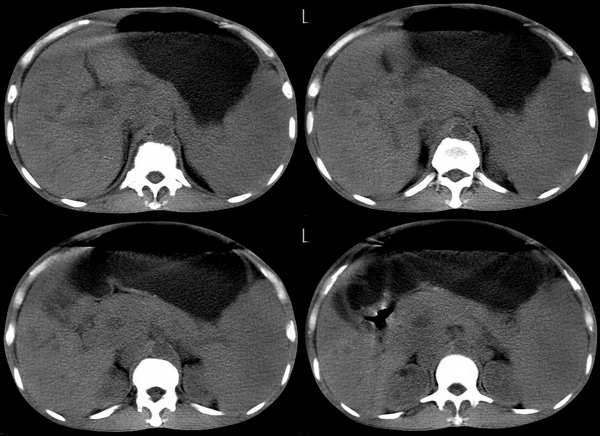

m 50y 腹部肿块两年来诊,现腹痛、腹胀。临床诊断“结肠癌并腹部转移”

第一遍从这个片子上!发现:病人脾脏增大!胰头部胆总管增粗!腹部肠腔扩张,前缘脂肪间隙消失,周围肠腔受压!腹膜后见多枚肿大淋巴结影!所以首先考虑胰头占位\\腹部转移!脾肿大.

胰头增大,右结肠肿块,腹膜后淋巴节融合成团,结合临床考虑结肠癌复发并胰头及腹膜后淋巴结转移并侵犯肠系膜动脉造成缺血性肠马匹